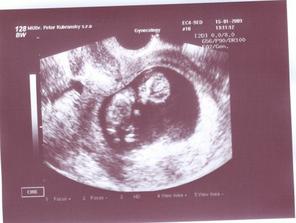

15.1.2009 sono + fotecka. bábätko robí kotrmelce, máva ručičkami a nožičkami (nech sa blázni, kým má miesto:D). všetko vyzerá byť ok. akurát na ľavom vaječníku mi dr.objavil cystu. hádam bude všetko ok.....

20tt morfologické UZV u Dr.Karabu - všetko vyzerá ok (dutiny), len bábätko je vraj menšie, ale nôžky má dlhé po mamine. O dva týždne ideme ešte raz, kvôli srdiečku.